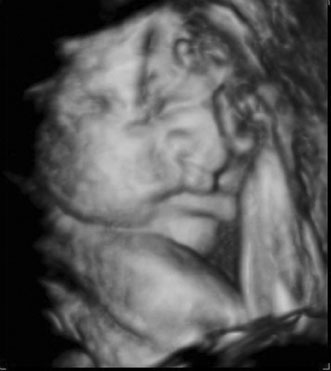

THREE-DIMENSIONAL ULTRASOUND

Three-dimensional ultrasound is currently investigational. It is most commonly used at tertiary care centers and is commercially available for patients to obtain a keepsake image of their unborn child. Potential advantages include the ability to visualize fetal anatomy better and possibly change a patient's diagnosis through improved visibility (Figs. 13 and 14). No confirmed adverse biologic effects on patients or instrument operators caused by exposure have been demonstrated.32

Fig. 13. Three-dimensional ultrasound image showing midline facial cleft. Image courtesy of GE Medical Systems.

Fig. 14. Three-dimensional ultrasound image of twin gestation. Image courtesy of GE Medical Systems.